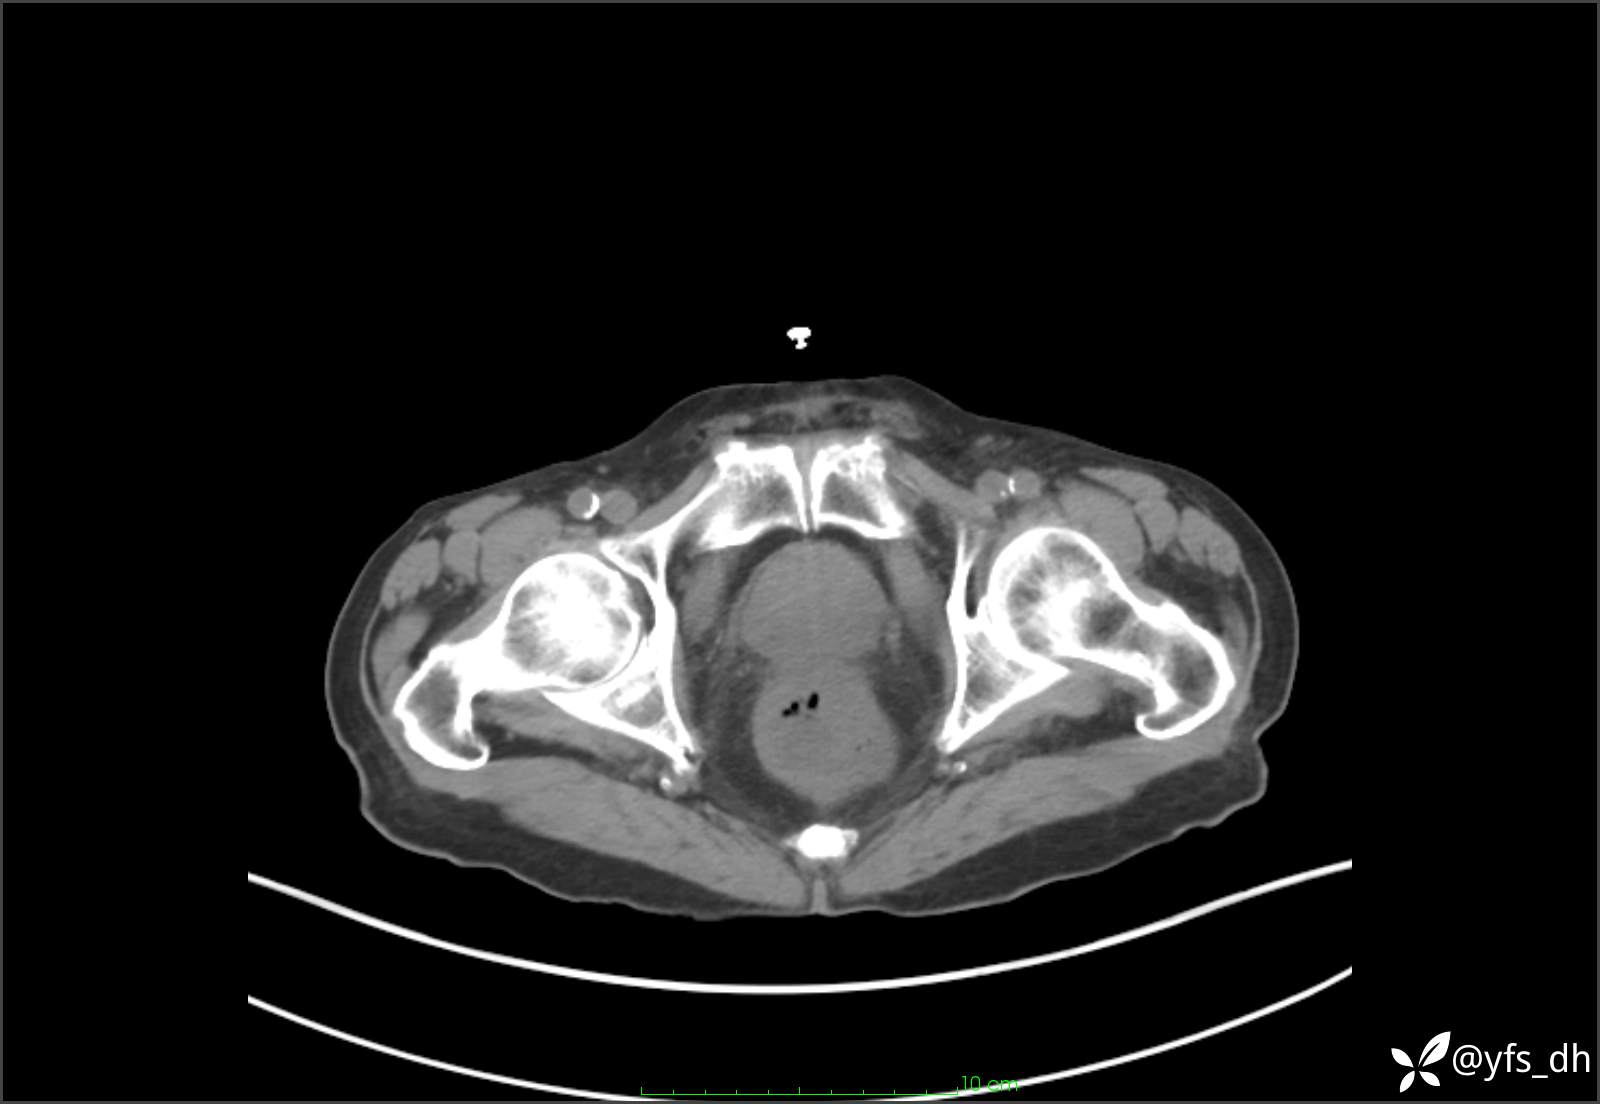

1.简要病史:患者4天前突发上腹部疼痛不适,但可以忍受。3小时前饭后突然加重,不能忍受后就诊。

2.简要手术记录:术中见腹盆腔大量肠液及粪便,乙状结肠中下段见一约3cm的破口。